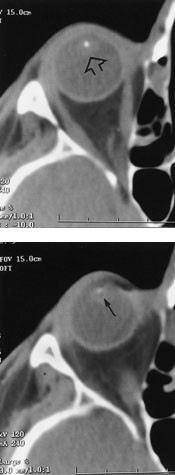

Nøyaktig lokalisasjon av intraokulære og intrabulbære fremmedlegemer er nødvendig preoperativt, og CT er en velegnet metode (9). Artefakter fra metalliske fremmedlegemer kan imidlertid gi inntrykk at fremmedlegemet er større enn dets virkelige mål (fig 6). MR er ofte kontraindisert fordi det sterke magnetfeltet kan bevege magnetiske fremmedlegemer og gi komplikasjoner.

CT gir best fremstilling av bein. Hvis det imidlertid er anamnestiske holdepunkter for at fremmedlegemet er av tre eller ikke-magnetisk materiale, er MR det beste valget. Til nøyaktig lokalisering av fremmedlegeme kreves snitt i to plan, noe som øker undersøkelsestiden og utsetter pasienten for større strålebelastning. Spiral-CT har mange fordeler i denne sammenheng – det gir kortere undersøkelsestid, reduserer stråledosen og gir høy kvalitet der bilder kan rekonstrueres i flere plan. CT har for en stor del erstattet tidligere ordinære røntgenbilder.